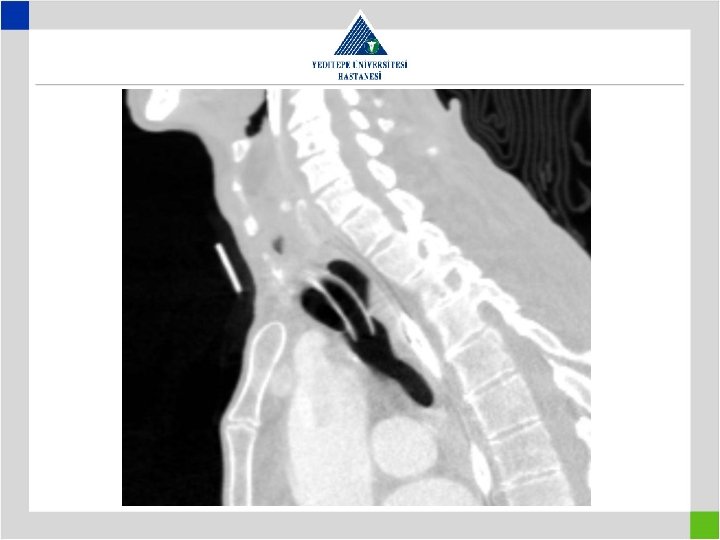

Diagnosis • Stenotic segment calculation to be correct • CT image in supine position may falsly indicate a preglottic stenosis – Overresection – increased anastomotic tension – restenosis • Pediatric trachea tolerates the tension poorly in comparison with adults – Insufficient resection – remaining fibrosis – restenosis